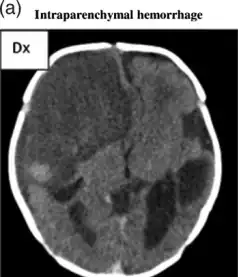

Intraparenchymal hemorrhage

| File:Multiple intraparenchymal hemorrhage.jpg | |

| Multiple intraparenchymal hemorrhage | |

CT scan shows a very large intraparenchymal haemorrhage with mass effect and occupying most of the right frontal lobe